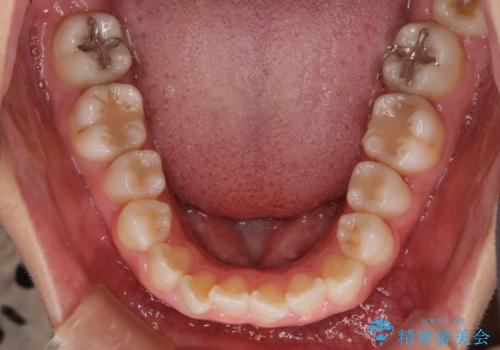

- ワイヤーではない矯正治療があると聞いたとのことで来院された患者様です。

長年前歯のデコボコを気にしていたもののワイヤー矯正に抵抗があり躊躇していたそうですが、インビザラインなら治療してみたいとのことで相談にいらっしゃいました。

インビザライン適用の歯列であったため、歯と歯の間を削るIPRを用いて改善することとしました。

お仕事柄、長時間のマウスピース装着が苦ではなかったので、歯列はすぐに整いましたが、ゆっくりとした交換頻度であったので、2年ほどの治療期間を要しました。